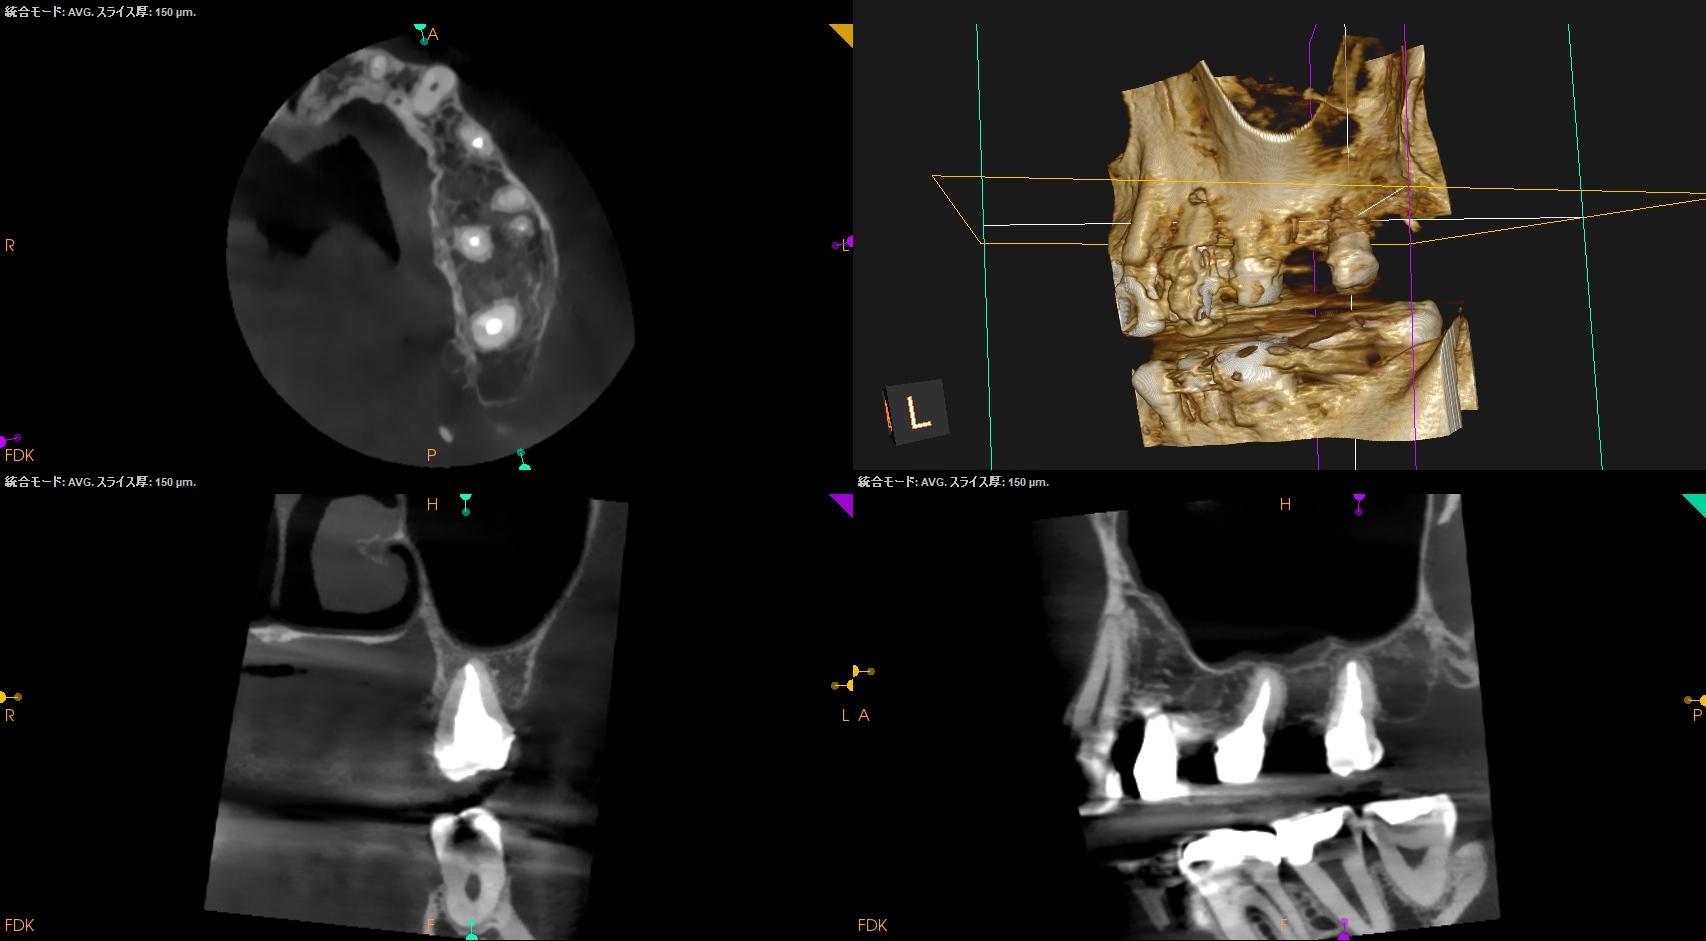

術後にPA, CBCTを撮影した。

#3

MB

DB

P

#14

#16